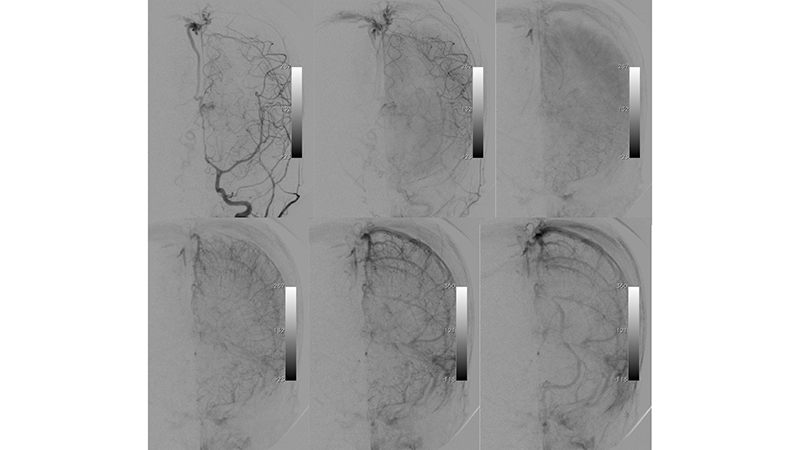

- Προσθιοπίσθια λήψη κατά την έγχυση στην αριστερή σπονδυλική αρτηρία. Ελέγχονται πολλαπλές μικροφίστουλες στο τοίχωμα της φλέβας του Γαληνού και μικρές αρτηριοφλεβώδεις επικοινωνίες στην χοριοειδή σχισμή (μικτού τύπου, τοιχωματικού και χοριοειδούς). Αρδεύονται από υποεπενδυματικούς τροφοφόρους κλάδους, εκ του Ρ1 τμήματος των οπισθίων εγκεφαλικών αρτηριών αμφοτερόπλευρα κυρίως δεξιά, που πορευόμενοι στο πλάγιο τοίχωμα της 3ης κοιλίας εκατέρωθεν, συναντούν την χοριοειδή σχισμή και εκείθεν αρδεύουν την αρτηριοφλεβώδη επικοινωνία (μαύρα βέλη). Επίσης συμμετέχουν οπισθιοπλάγιοι έσω χοριοειδείς (διακεκομμένο κόκκινο βέλος) και οπισθιοπλάγιοι έξω χοριοειδείς κλάδοι (κόκκινο βέλος) από το Ρ2 και Ρ3 τμήματα των οπισθίων εγκεφαλικών αρτηριών αμφοτερόπλευρα, που δια της χοριοειδούς σχισμής καταλήγουν στο οπίσθιο τοίχωμα της φλέβας του Γαληνού. Διακρίνεται επίσης η απόφραξη των εγκαρσίων κόλπων και η αναστροφή της ροής προς το εγκεφαλικό φλεβικό δίκτυο με συμφόρηση των εγκεφαλικών φλεβών.

- Πλαγία λήψη κατά την έγχυση στην αριστερή σπονδυλική αρτηρία. Τροφοφόροι θαλαμοδιατιτραίνοντες (διακεκομμένο μαύρο βέλος) και υποεπενδυματικοί κλάδοι (διακεκομμένο μπλέ βέλος), εκ της οπισθίας αναστομωτικής και του Ρ1 τμήματος των οπισθίων εγκεφαλικών αρτηριών, που πορευόμενοι στο πλάγιο τοίχωμα της 3ης κοιλίας εκατέρωθεν, συναντούν την χοριοειδή σχισμή και εκείθεν αρδεύουν την αρτηριοφλεβώδη επικοινωνία (μαύρα βέλη). Παρατηρείται αναστροφή της ροής στον άνω οβελιαίο κόλπο με φλοιώδη παλινδρόμηση προς τα εγκεφαλικά ημισφαίρια αμφοτερόπλευρα (κόκκινα βέλη). Οι εγκάρσιοι κόλποι αποφράσσονται, και μέσω των περιμεσεγκεφαλικών φλεβών παρατηρείται παροχέτευση προς το περιμυελικό φλεβικό δίκτυο του νωτιαίου μυελού (μπλέ βέλη) το οποίο παρουσιάζει εκσεσημασμένη συμφόρηση αλλά και διά του άνω λιθοειδούς κόλπου προς τον σηραγγώδη κόλπο (μαύρα βέλη).

- Αξονική τομογραφία με σκιαγραφικό και αγγειογραφία του σπονδυλοβασικού συστήματος σε πλάγια λήψη. Διακρίνεται κατιούσα φλεβική παροχέτευση προς το περιμυελικό φλεβικό δίκτυο του νωτιαίου μυελού (μπλέ βέλη) το οποίο παρουσιάζει εκσεσημασμένη συμφόρηση.